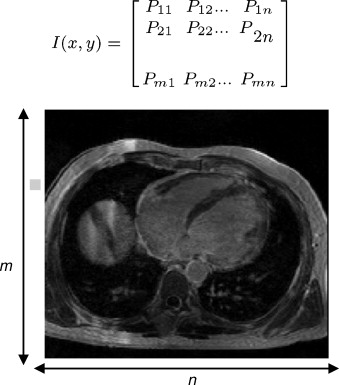

Cada corte adquirido en una sesión de diagnóstico por imagen es representado por una matriz bidimensional de tamaño m ×n ( fig. 2 ), donde cada elemento Px,y de la matriz es conocido como pixel (picture element) , n representa el número de pixels a lo ancho de la imagen y m es el número de pixels a lo largo. En la figura, cada elemento Px,y representa un valor en escala de gris, el cual refleja el grado de atenuación del haz radiológico sobre el tejido humano.

|

|

|

Figura 2. Representación bidimensional de un corte ortogonal de una imagen médica, donde cada elemento Px,y es un pixel cuyo valor es obtenido por el grado de atenuación de un haz radiológico sobre el tejido humano. |

La reconstrucción 3D de estos cortes iniciales es obtenida por el apilamiento paralelo de o cortes de la misma resolución (tamaño m × n pixels ), lo cual es representado por una matriz 3D de dimensiones m × n × o, donde cada elemento Vx,y,z de esta matriz es denominado voxel , el cual es el elemento básico de un volumen ( fig. 3 ). En la figura, se presenta la representación matricial del primer y último corte de la imagen 3D.

|

|

|

Figura 3. Representación tridimensional de una imagen médica, donde cada elemento Vx,y,z de la matriz 3D es un voxel . |

Para mantener la relación del tamaño del volumen reconstruido con el tamaño real del tejido, se tiene en cuenta el espaciado de cada voxel (voxel spacing ) que conforma el volumen, el cual es obtenido de la información incluida en la imagen médica. El procesamiento de las imágenes se lleva a cabo procesando los valores de niveles de gris contenido en la matriz que representa la imagen.